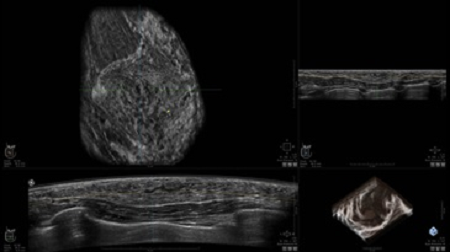

УЗИ-аппарат

GE INVENIA ABUS 2.0

GE INVENIA ABUS – это современный УЗИ аппарат, который создан для точной и эффективной диагностики сканирования с высокой плотностью молочных желез. Выявляемость патологий раковых и предраковых стадий заболевания составляет 55%, что в конечном счете позволяет ставить врачу точные и своевременные диагнозы. Традиционные методы использования маммографии не показывают такой выявляемости, ограничиваясь лишь 3-38%.

УЗИ-аппарат GE INVENIA ABUS позволяет проводить максимально операторонезависимые процедуры, что значительно снижает риск неправильной постановки диагноза и сопутствующие издержки на обработку информации. Система готовит отчет в течение 3-х минут после сканирования, это безусловное преимущество по сравнению с обычным УЗИ сканером.

• датчик с изогнутой апертурой для качественного исследования

• сканирование одной грудной железы в трех проекциях не более 60 сек.;

• обработка результатов за три минуты.

Данное устройство классифицируется, как стационарное, используемое в многопрофильных клиниках, женских консультациях, медицинских центрах. Вес без учета дополнительного оборудования составляет 105 кг. Удобная колесная база позволяет оперативно маневрировать в ограниченных пространствах, в том числе передвигать устройство в коридорах клиники. Большой 17-ти дюймовый монитор с широкими углами обзора выводит максимально качественную картинку в формате Full HD.

• Получение объемных 3D изображений с возможностью покадрового просмотра

• Отображение объемных 3D ультразвуковых изображений, которые состоят из традиционных поперечных и воссозданных коронарных и сагиттальных проекций

• Возможность отображения полного 3D изображения

• Стандартизованная ориентация изображения: «толстый срез» в коронарной плоскости; поперечная; сагиттальная плоскость; радиальный и антирадиальный поворот изображения; просмотр исключительно области интереса